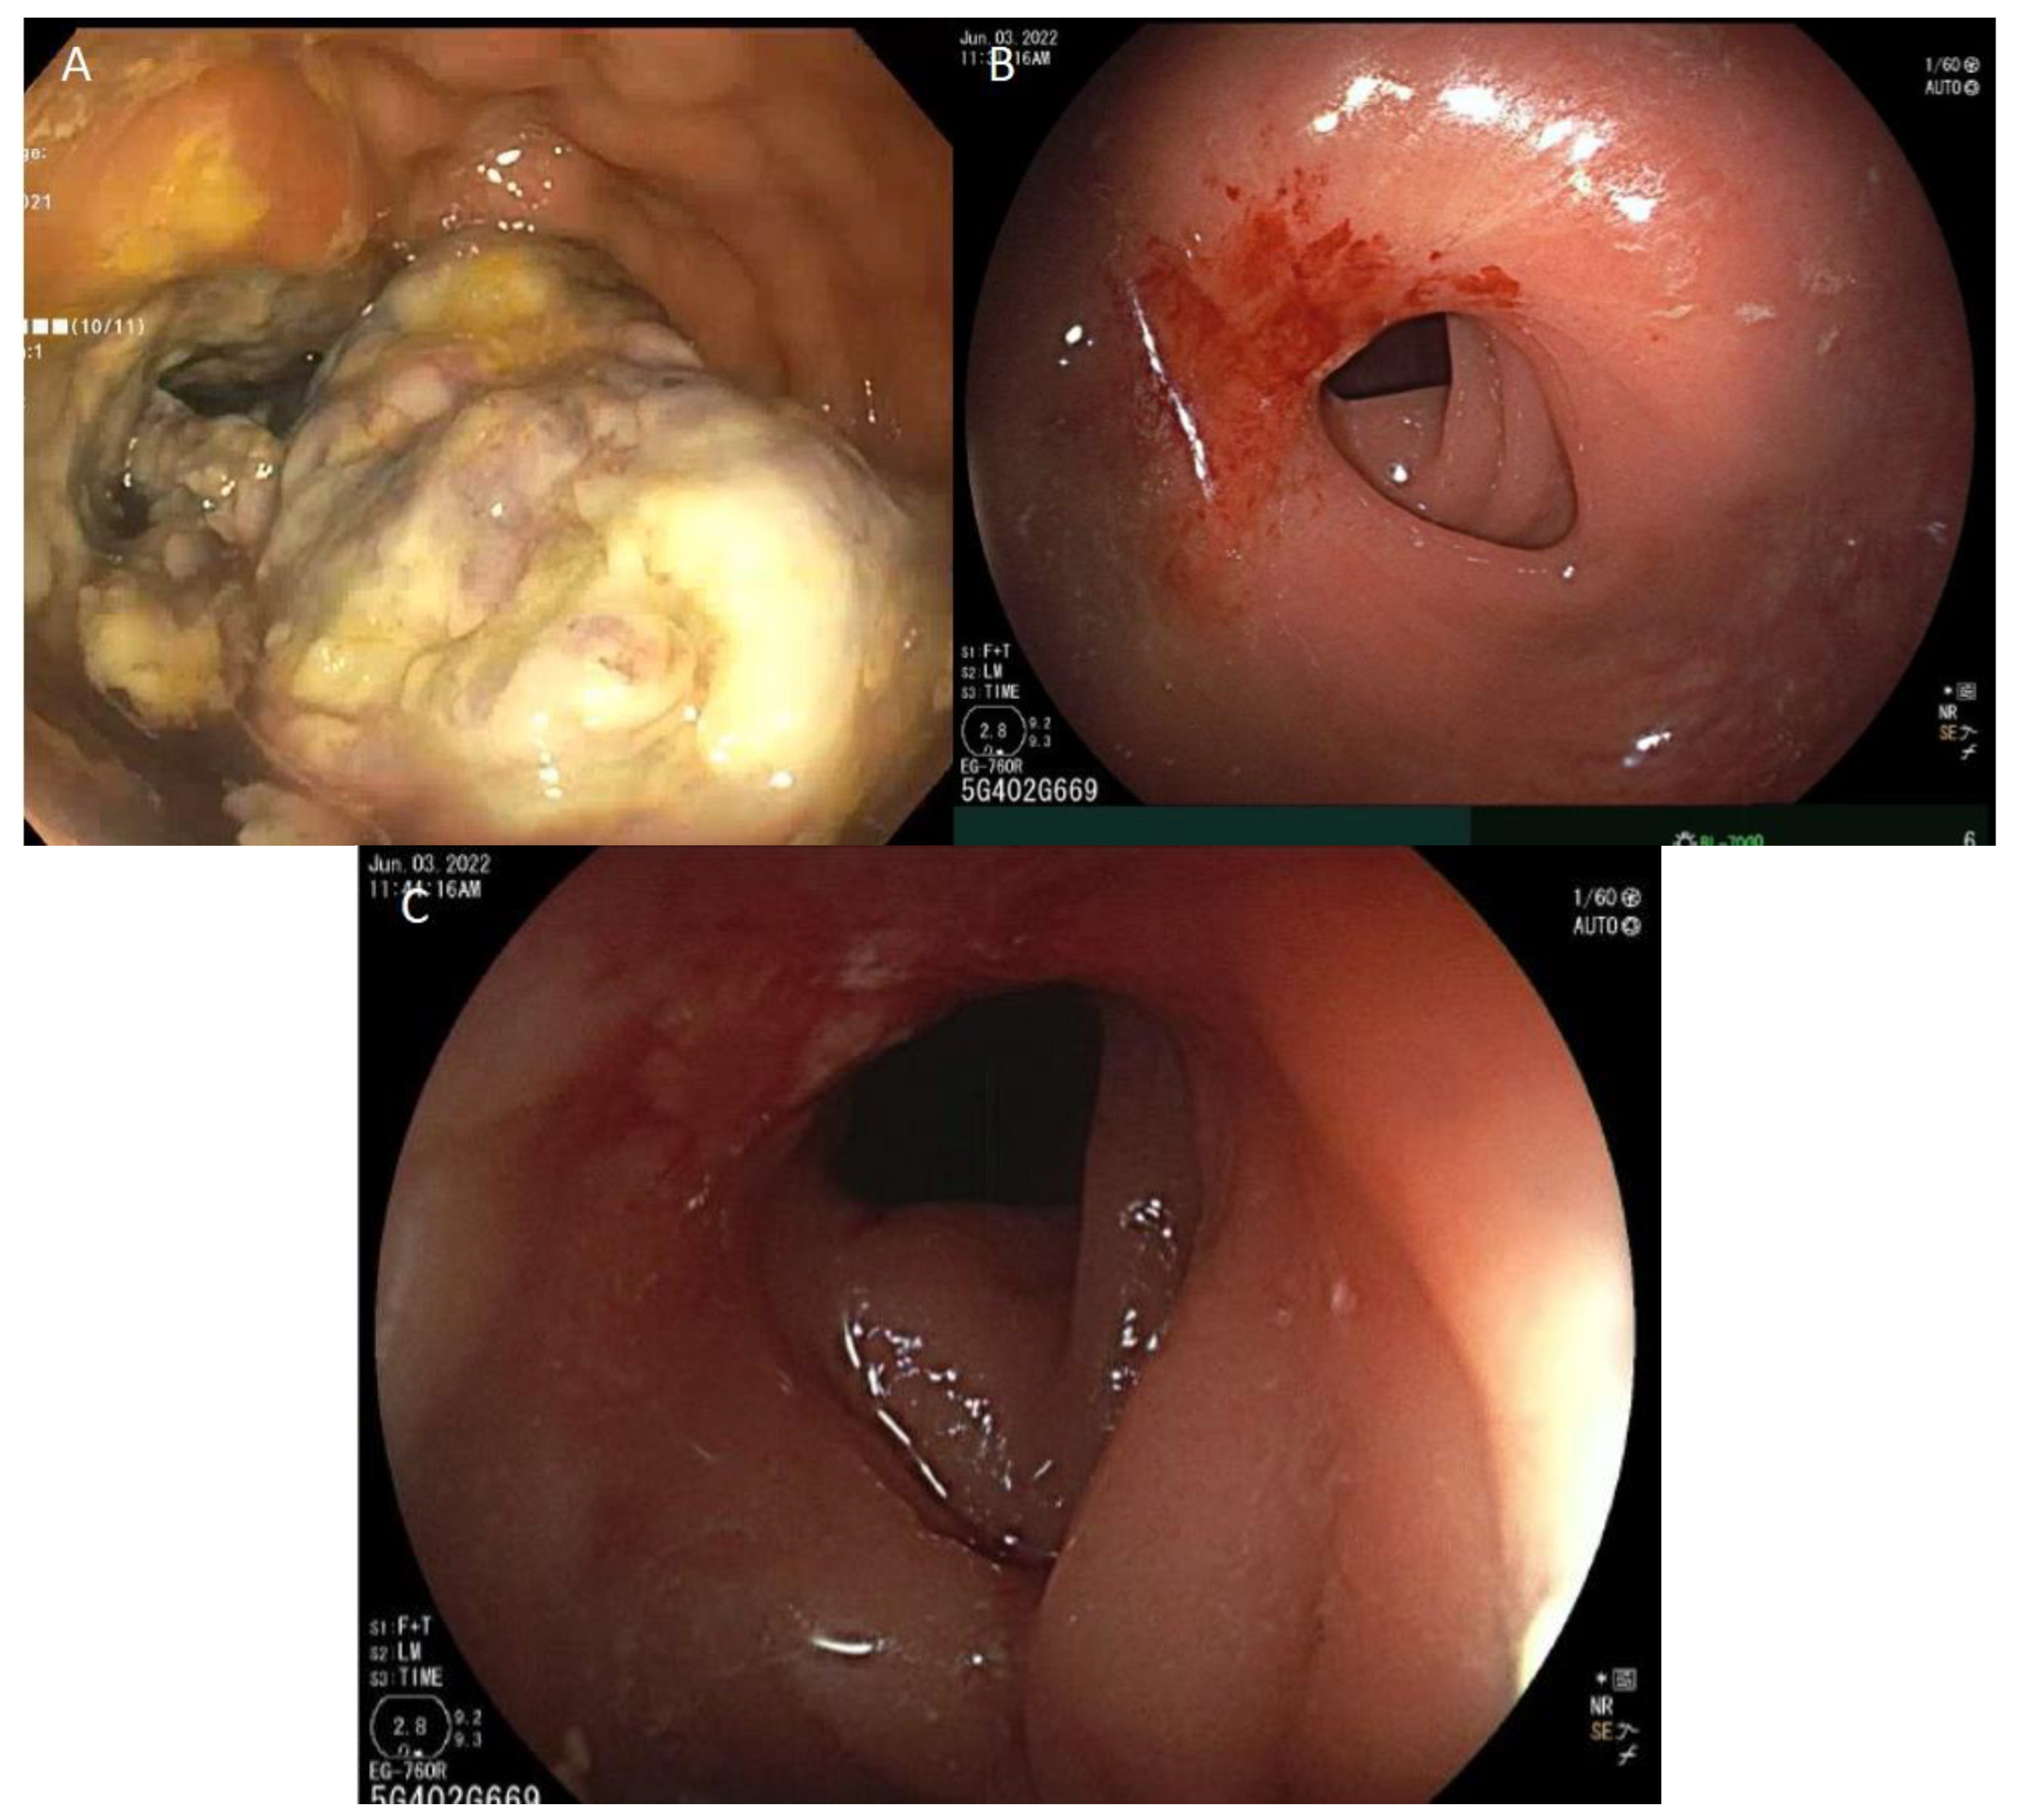

6. ICI Toxicity Management

7. Response Assessment and Management of Immunotherapy-Related Rectal Stricture